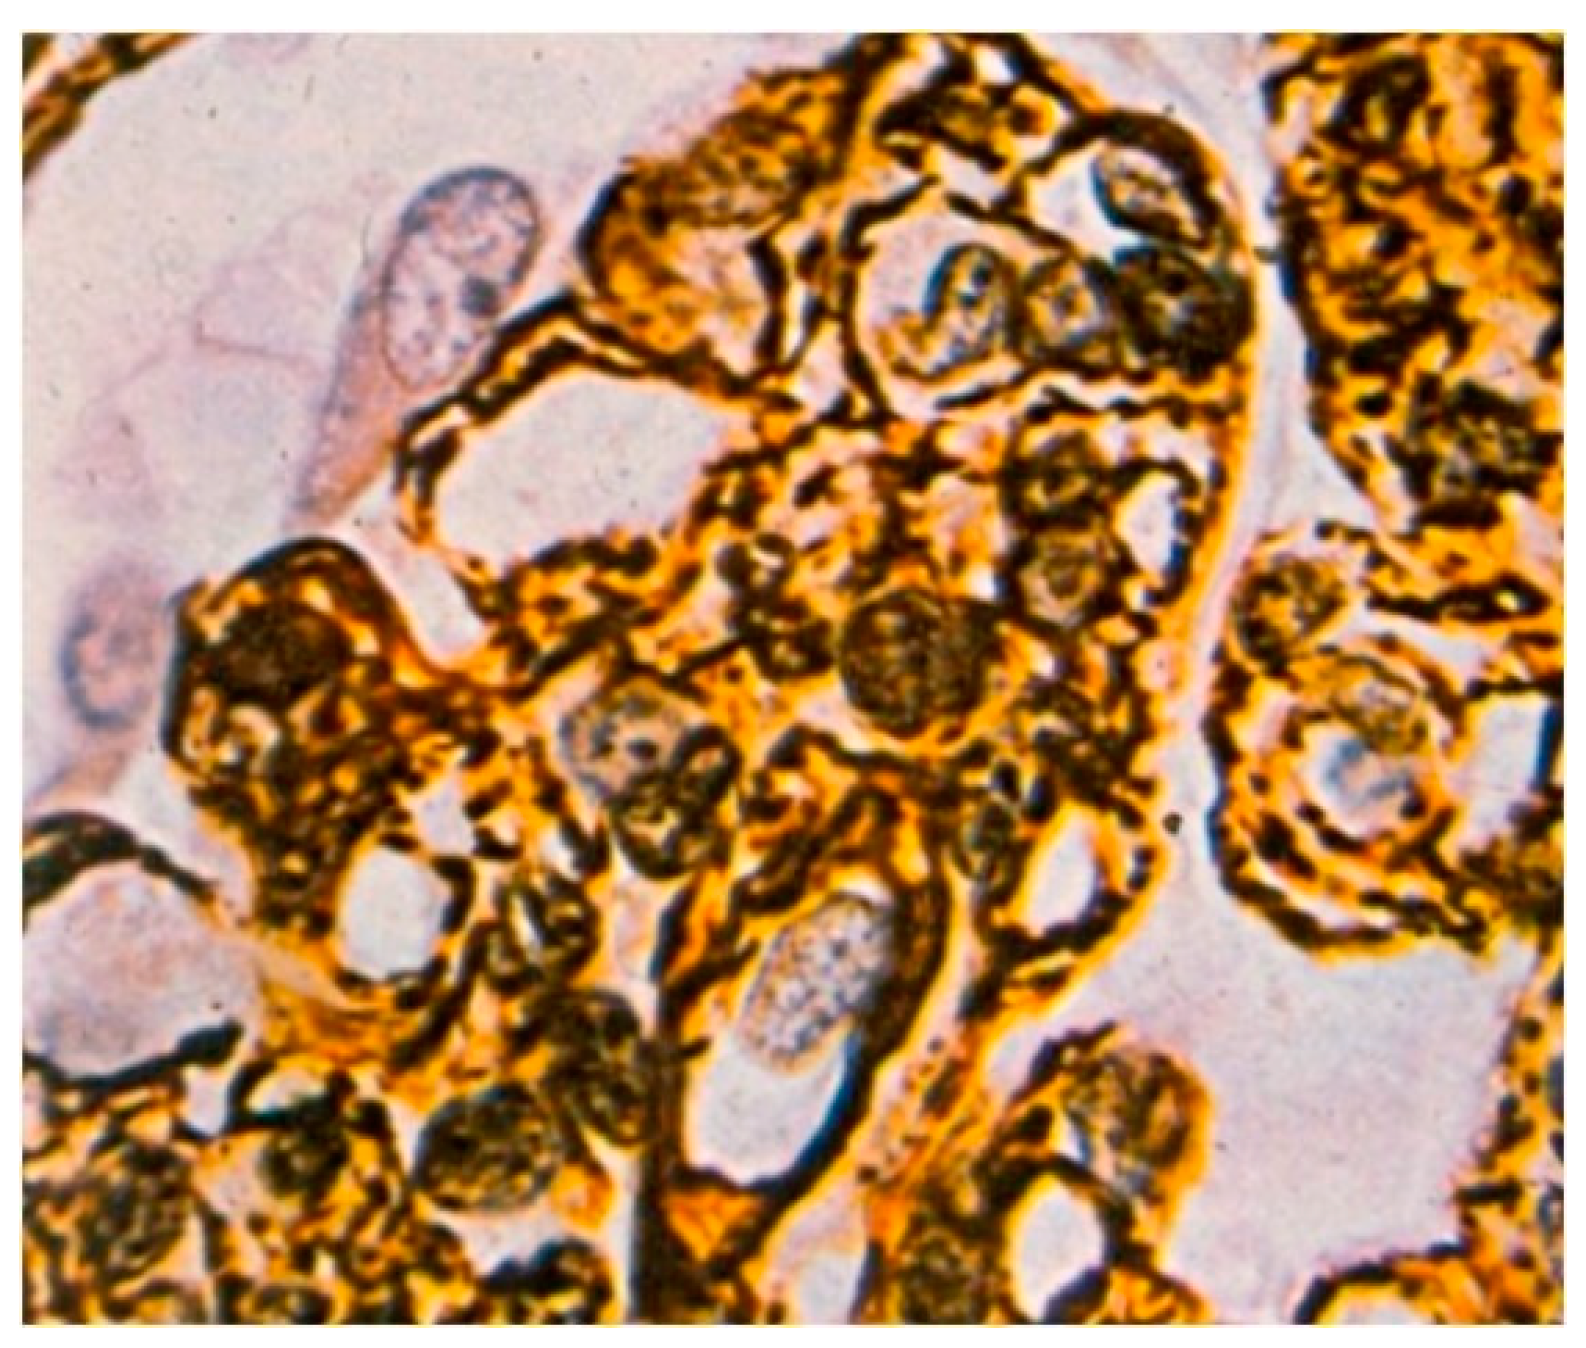

Light microscopy showed an increased number of cells in the glomeruli and an adventitia of the mesangial matrix. The kidney glomeruli were characterized by a lobular structure (Figure 4). Jones’ stain method highlighted the double-contouring of the capillary loop walls (Figure 5).

Figure 5. Double-contouring of the walls of the capillary loops. Impregnation with silver-containing salt according to a Jones stain, 400× magnification.